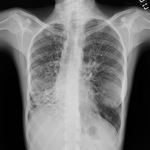

Radiografia de tórax com ausência de afunilamento normal, produzindo linha de trem

Dos arquivos do Dr. Sangeeta M. Bhorade; uso autorizado